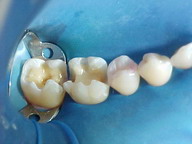

Fase laboratorial ONLAY ARTGLASS

ANTES DEPOIS

Caso acima, em outro ângulo, no momento da cimentação do ONLAY